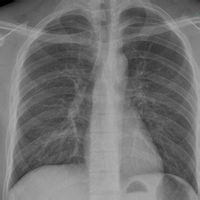

概述 發病機制 病理 症狀體徵 診斷鑑別肺不張(atelectasis)系指一個或多個肺段或肺葉的容量或含氣量減少。由於肺泡內氣體吸收肺不張通常伴有受累區域的透光度降低,鄰近結構(支氣管、肺血...